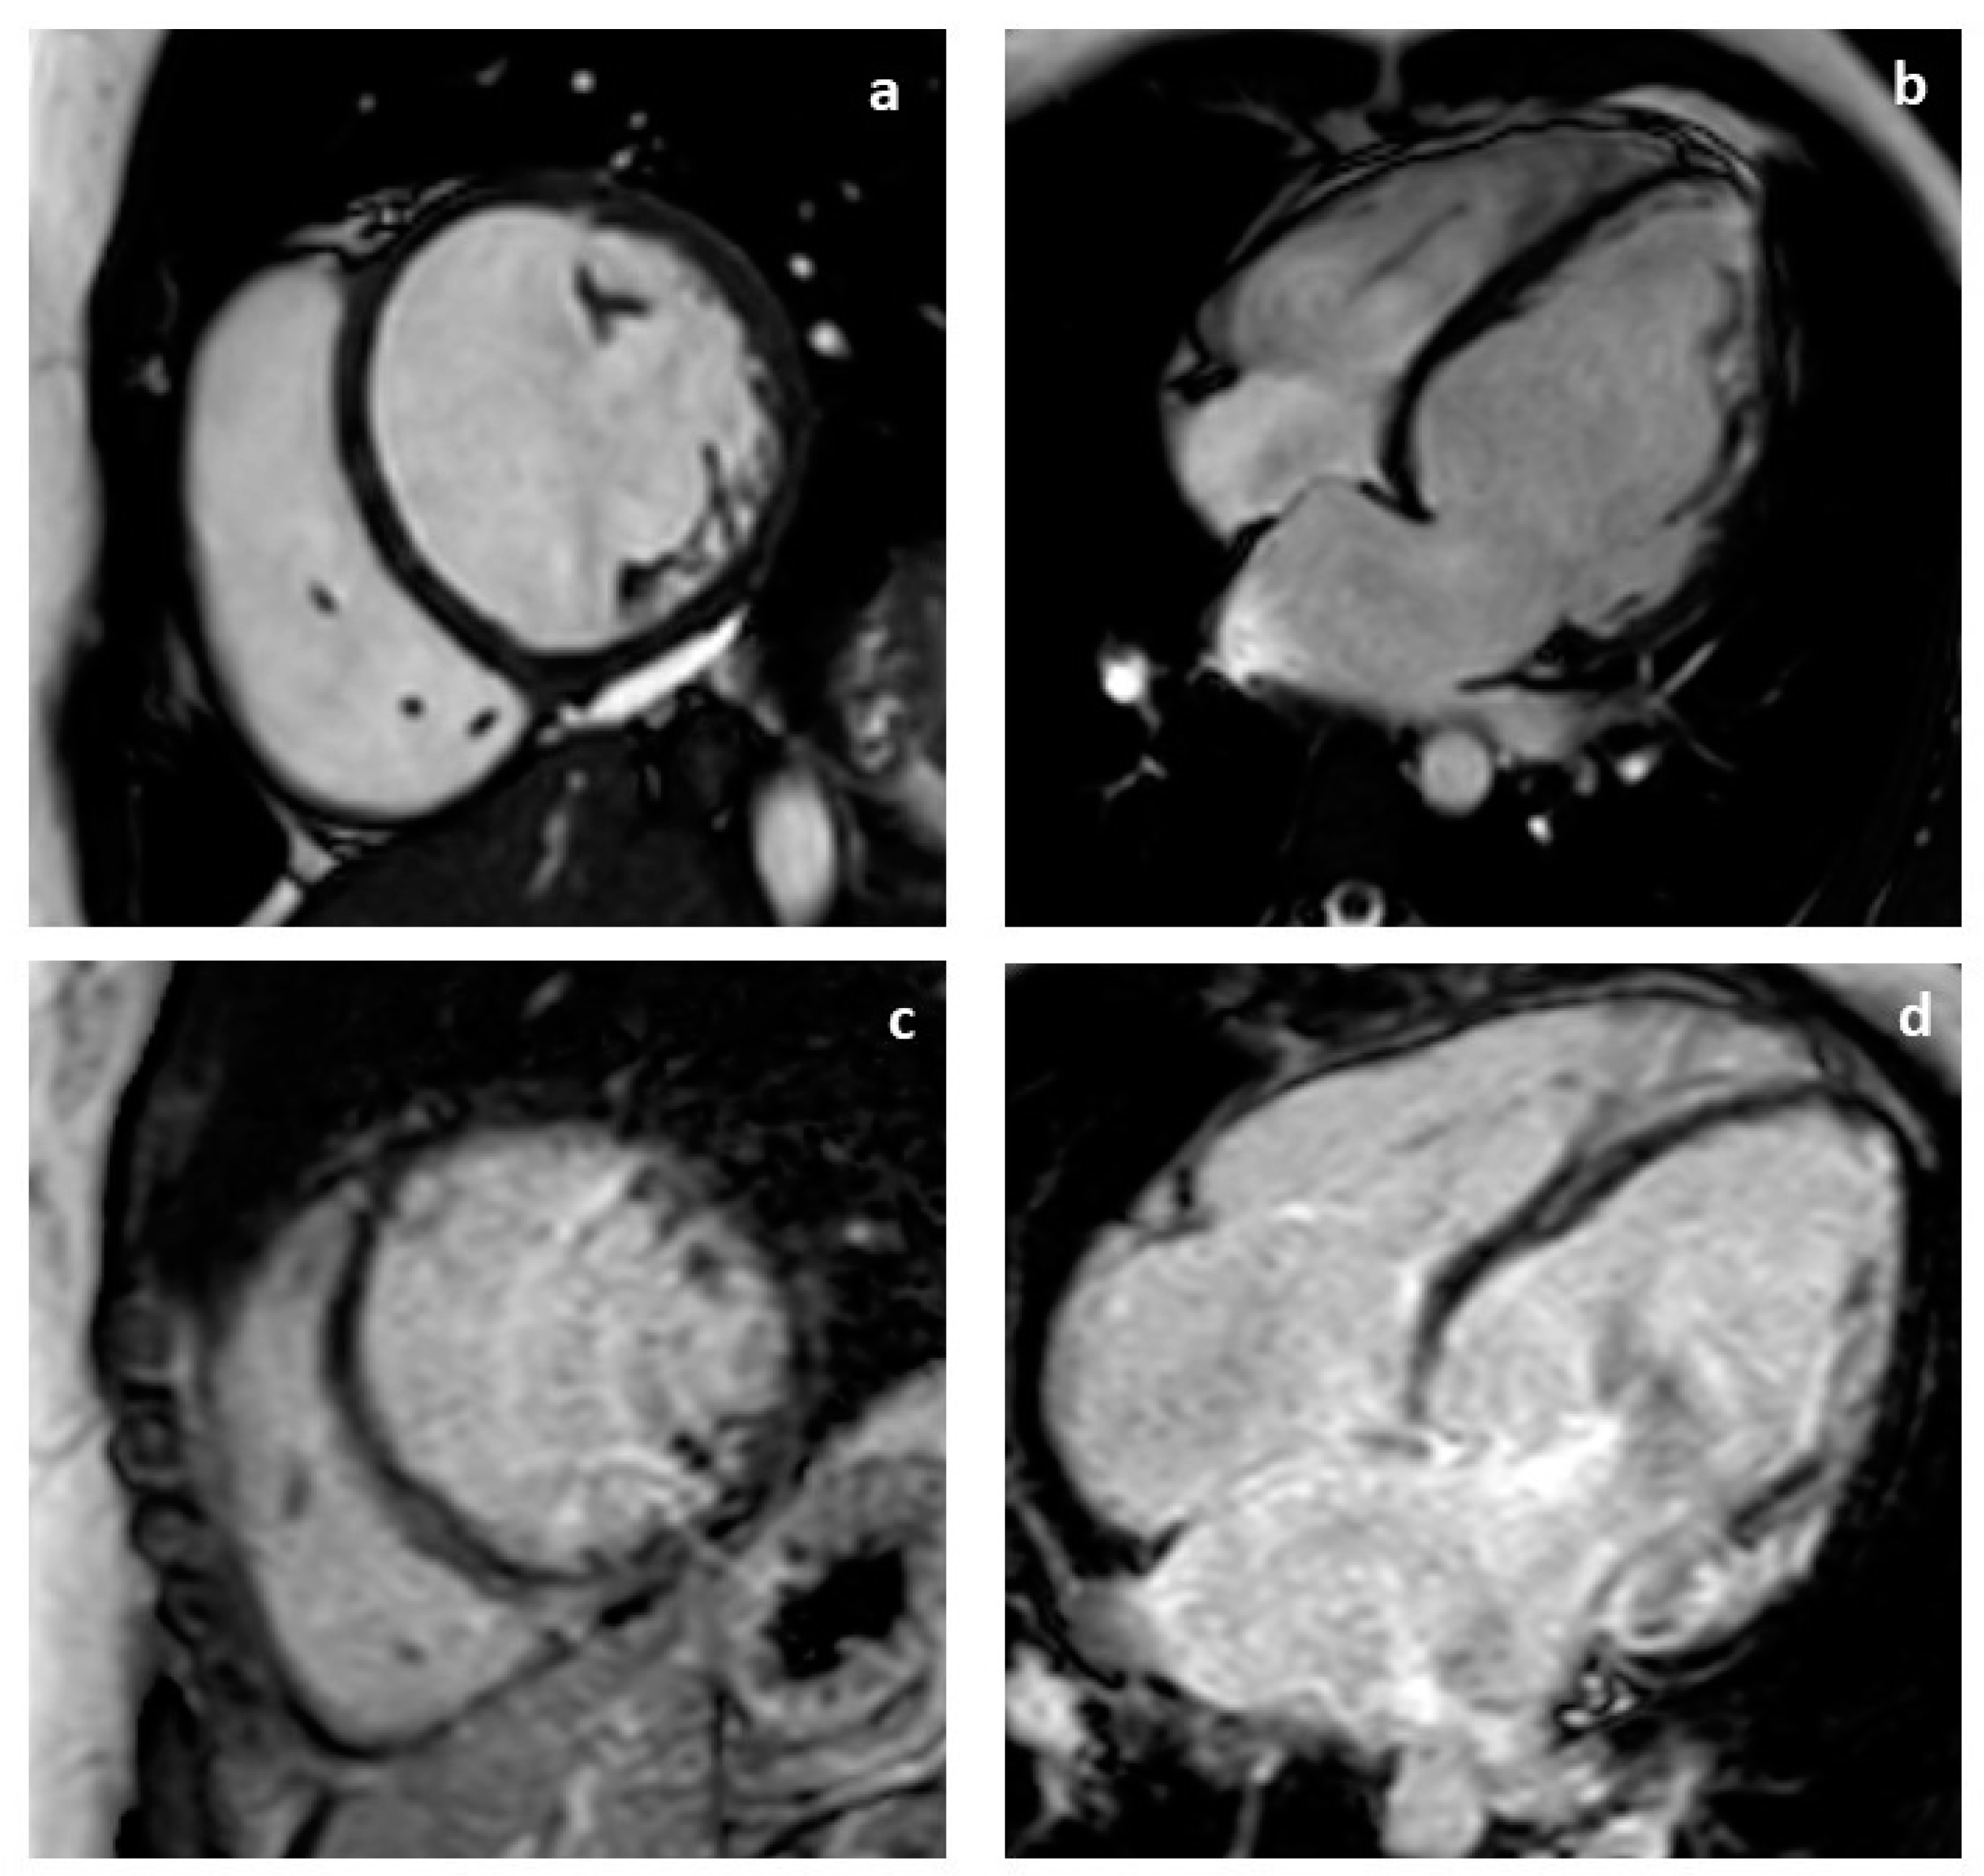

2. Case Presentation

2.1. Proband Clinical Characteristics